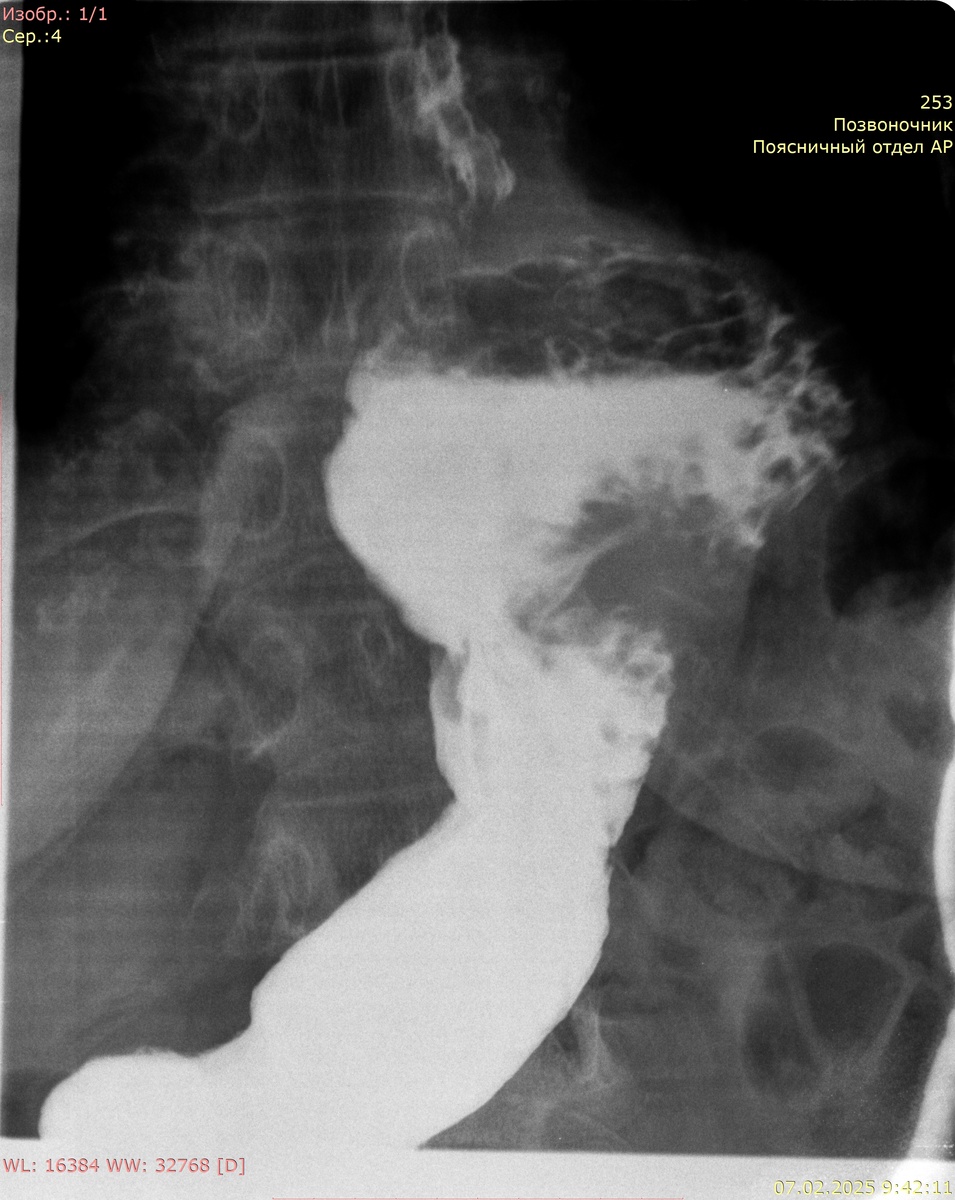

Рентгенография желудка с сульфатом Ва:

Кардиальный жом функционирует. Желудок деформирован, объем обычный, до 1/2 объема в проекции грудной полости. Контуры желудка ровные, отвесные, участков деформации не выявлено. Рельеф слизистой не изменен, складки не утолщены. Контраст своевременно поступает в ДПК. В положении стоя определяется пролабирование кардиальных складок выше диафрагмы размерами 80 мм х 63 мм (лежа до 118 мм х 88 мм).

Заключение: фиксированная грыжа пищеводного отверстия диафрагмы 4 ст.

Желудок стоя